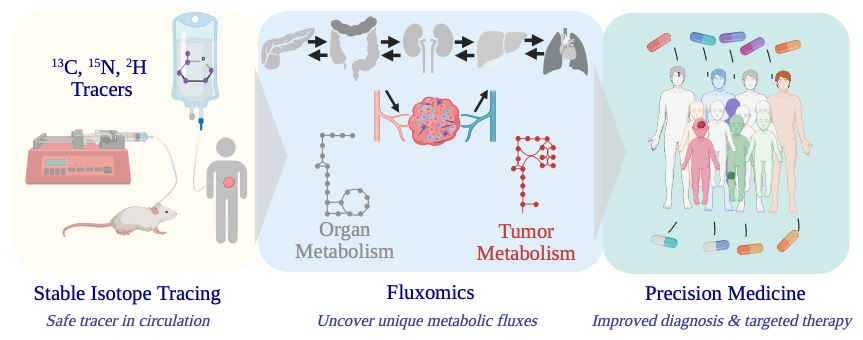

Our Solution- Stable Isotope Tracing

Zurich Trace is a platform that brings stable isotope tracing directly into the patient setting. By administering safe, non-radioactive, stable isotope-labeled nutrients and tracing their transformation through metabolic networks in blood, tissue, or other samples, we capture true metabolic activity.

With minimal invasiveness and high-resolution analytics, stable isotope tracing bridges the gap between advanced metabolic science and patient care.

How Stable Isotope Tracing Works

Step (1)

Administer stable isotope-labeled nutrients (e.g., 13C-glucose, 15N-glutamine)

Step (2)

Collect blood, urine, or tissue samples (alternative in-patient NMR)

Step (3)

Analyze with LC-MS or NMR

Step (4)

Interpret metabolic flux using custom-built modeling software (e.g., SUMOFLUX)

Clinical and Research Applications